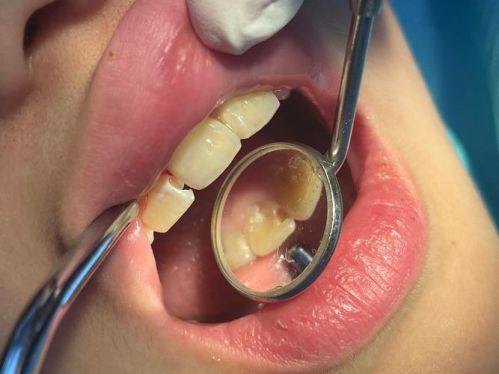

烤瓷牙:提供高质量烤瓷牙修复服务,修复牙齿功能与美观

韩国江南人爱牙科烤瓷牙:1200元起/颗